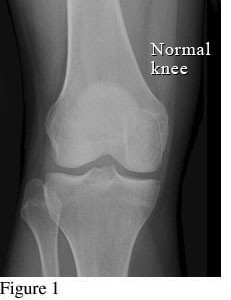

Hình ảnh so sánh giữa khớp bình thường và khớp bị thoái hóa khớp gối

Để phân biệt các giai đoạn của bệnh thoái hóa khớp gối, cần dựa vào phim X- quang theo tiêu chuẩn chẩn đoán thoái hoá khớp của Kellgren và Lawrence như sau:

Hình ảnh khớp gối trên phim X-quang: Khe khớp gần như bình thường, có thể có gai xương nhỏ.

Ở giai đoạn đầu tiên, khớp gối chưa có dấu hiệu bất thường cho thấy bị thoái hóa khớp gối. Bệnh nhân đi lại bình thường, chưa xuất hiện cơn đau khớp hoặc có thể chỉ đau khớp gối khi đứng lên ngồi xuống, ngồi xổm, lên xuống cầu thang. Khớp gối cũng chưa bị sưng và không biến dạng. Nếu chụp thêm MRI có thể thấy khớp gối gần như bình thường.